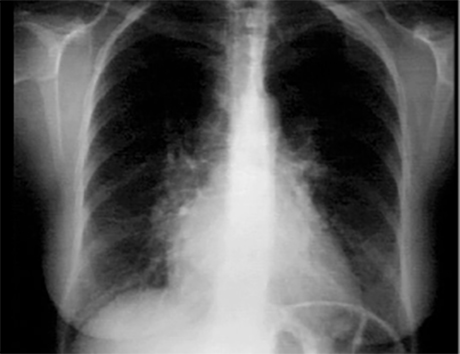

PA

These chest X rays show right ventricular enlargement and left atrial enlargement. The PA view demonstrates left atrial enlargement reflected by the

double contour within the heart border,

an elevated

left mainstem bronchus

and an enlarged

left atrial appendage

causing straightening of the left heard border. Note also that the

cardiothoracic ratio

is greater than 50%, reflecting cardiomegaly. In the lateral view,